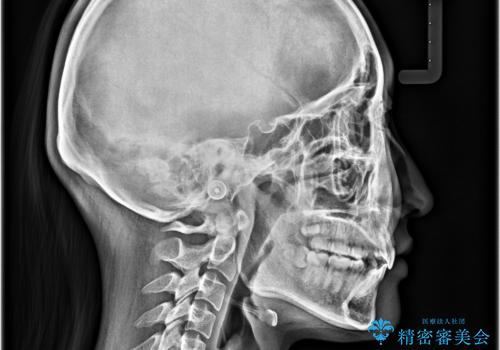

- 上顎前歯の突出感を気にして来院された患者様です。

上下左右第一小臼歯4本を抜歯して、積極的に口元を引っ込めるよう、ワイヤー装置にて矯正治療を行うこととしました。

抜歯矯正により、下唇が前方に突出した感覚が大幅に改善されました。